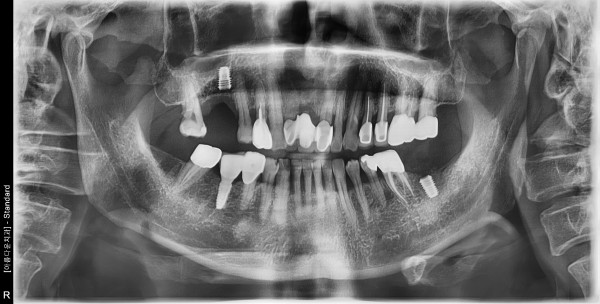

60대 남성 임플란트 식립